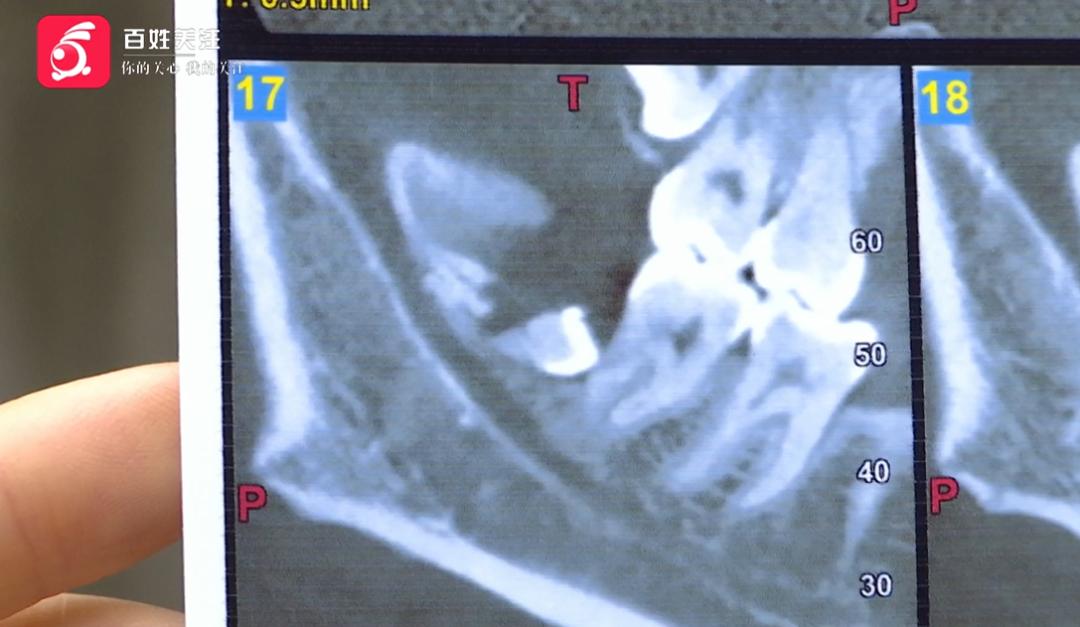

羅女士:從片子上來看,牙齒沒拔出來,還有一半。

記者:損傷怎么看出來?

羅女士:你看這邊是好的,骨頭還在,這邊骨頭斷裂了

。